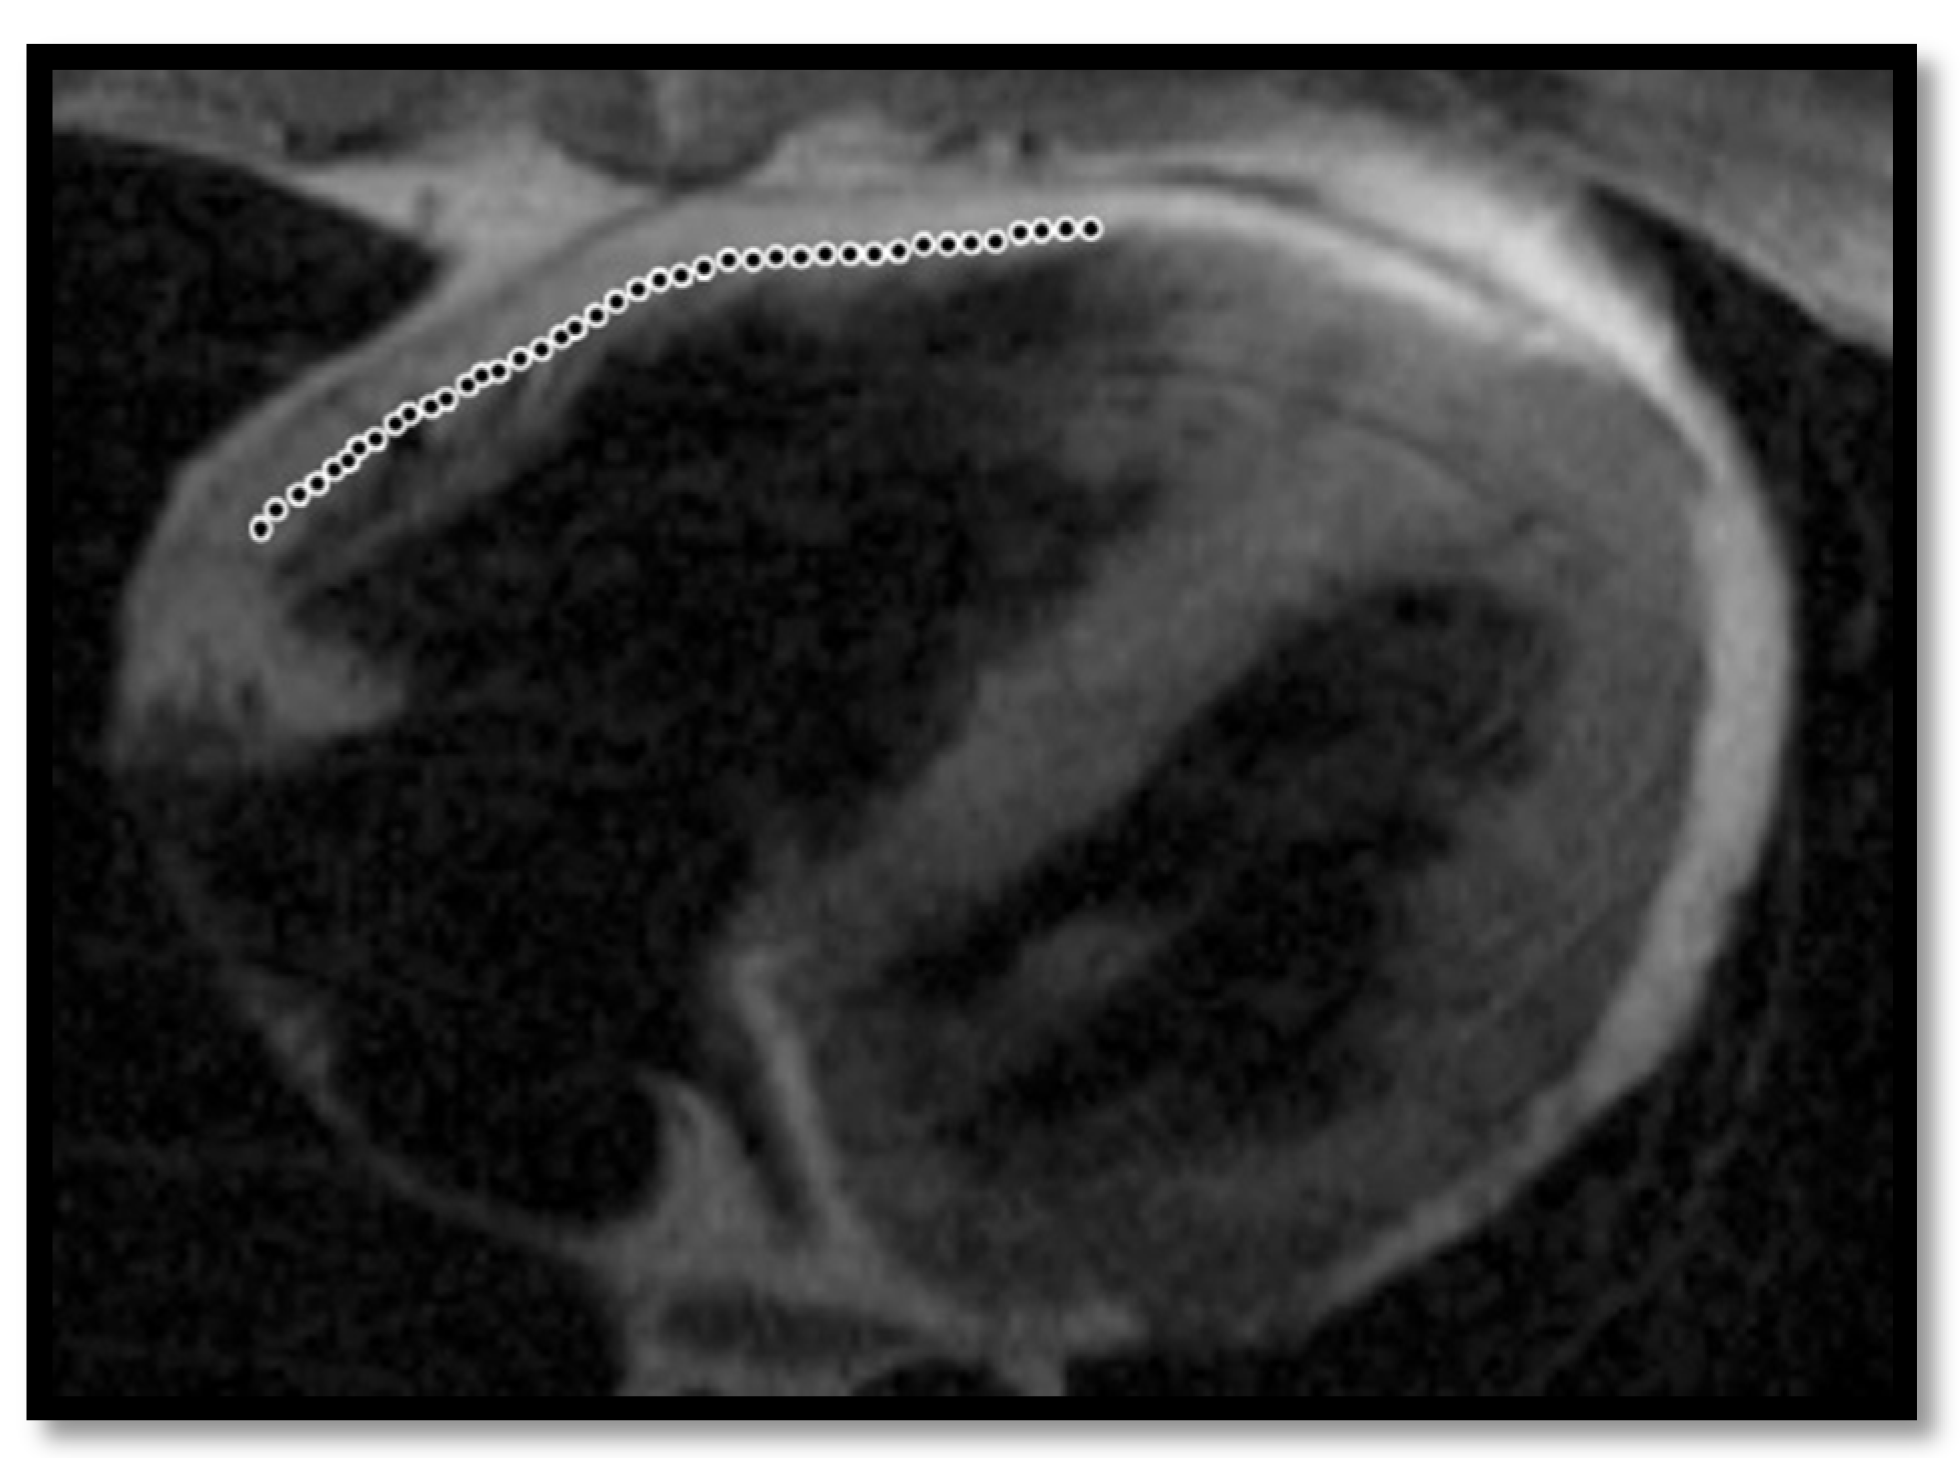

- RV dilation is also a key element for the diagnosis of ARVC. It can be segmental or global. Segmental expansion can affect only the RVOT or parts of the RV such as the basal free wall or the middle third of the free wall. It is a diagnostic criterion with high sensitivity and specificity for ARVC (Figure 3). Only the global dilation of RV is considered a diagnostic criterion for ARVC because segmental dilatation is rather difficult to interpret [12,45].

- Thinning of the RV wallThis is a component that was not included in the Task Force Criteria for the diagnosis of ARVC [12,45]. This is because the reports of different authors were not consistent with regards to the thinning or thickening of the ventricular wall. Therefore, thinning of the wall is considered pathological only when associated with contraction abnormalities at the same level [48] (Figure 6).